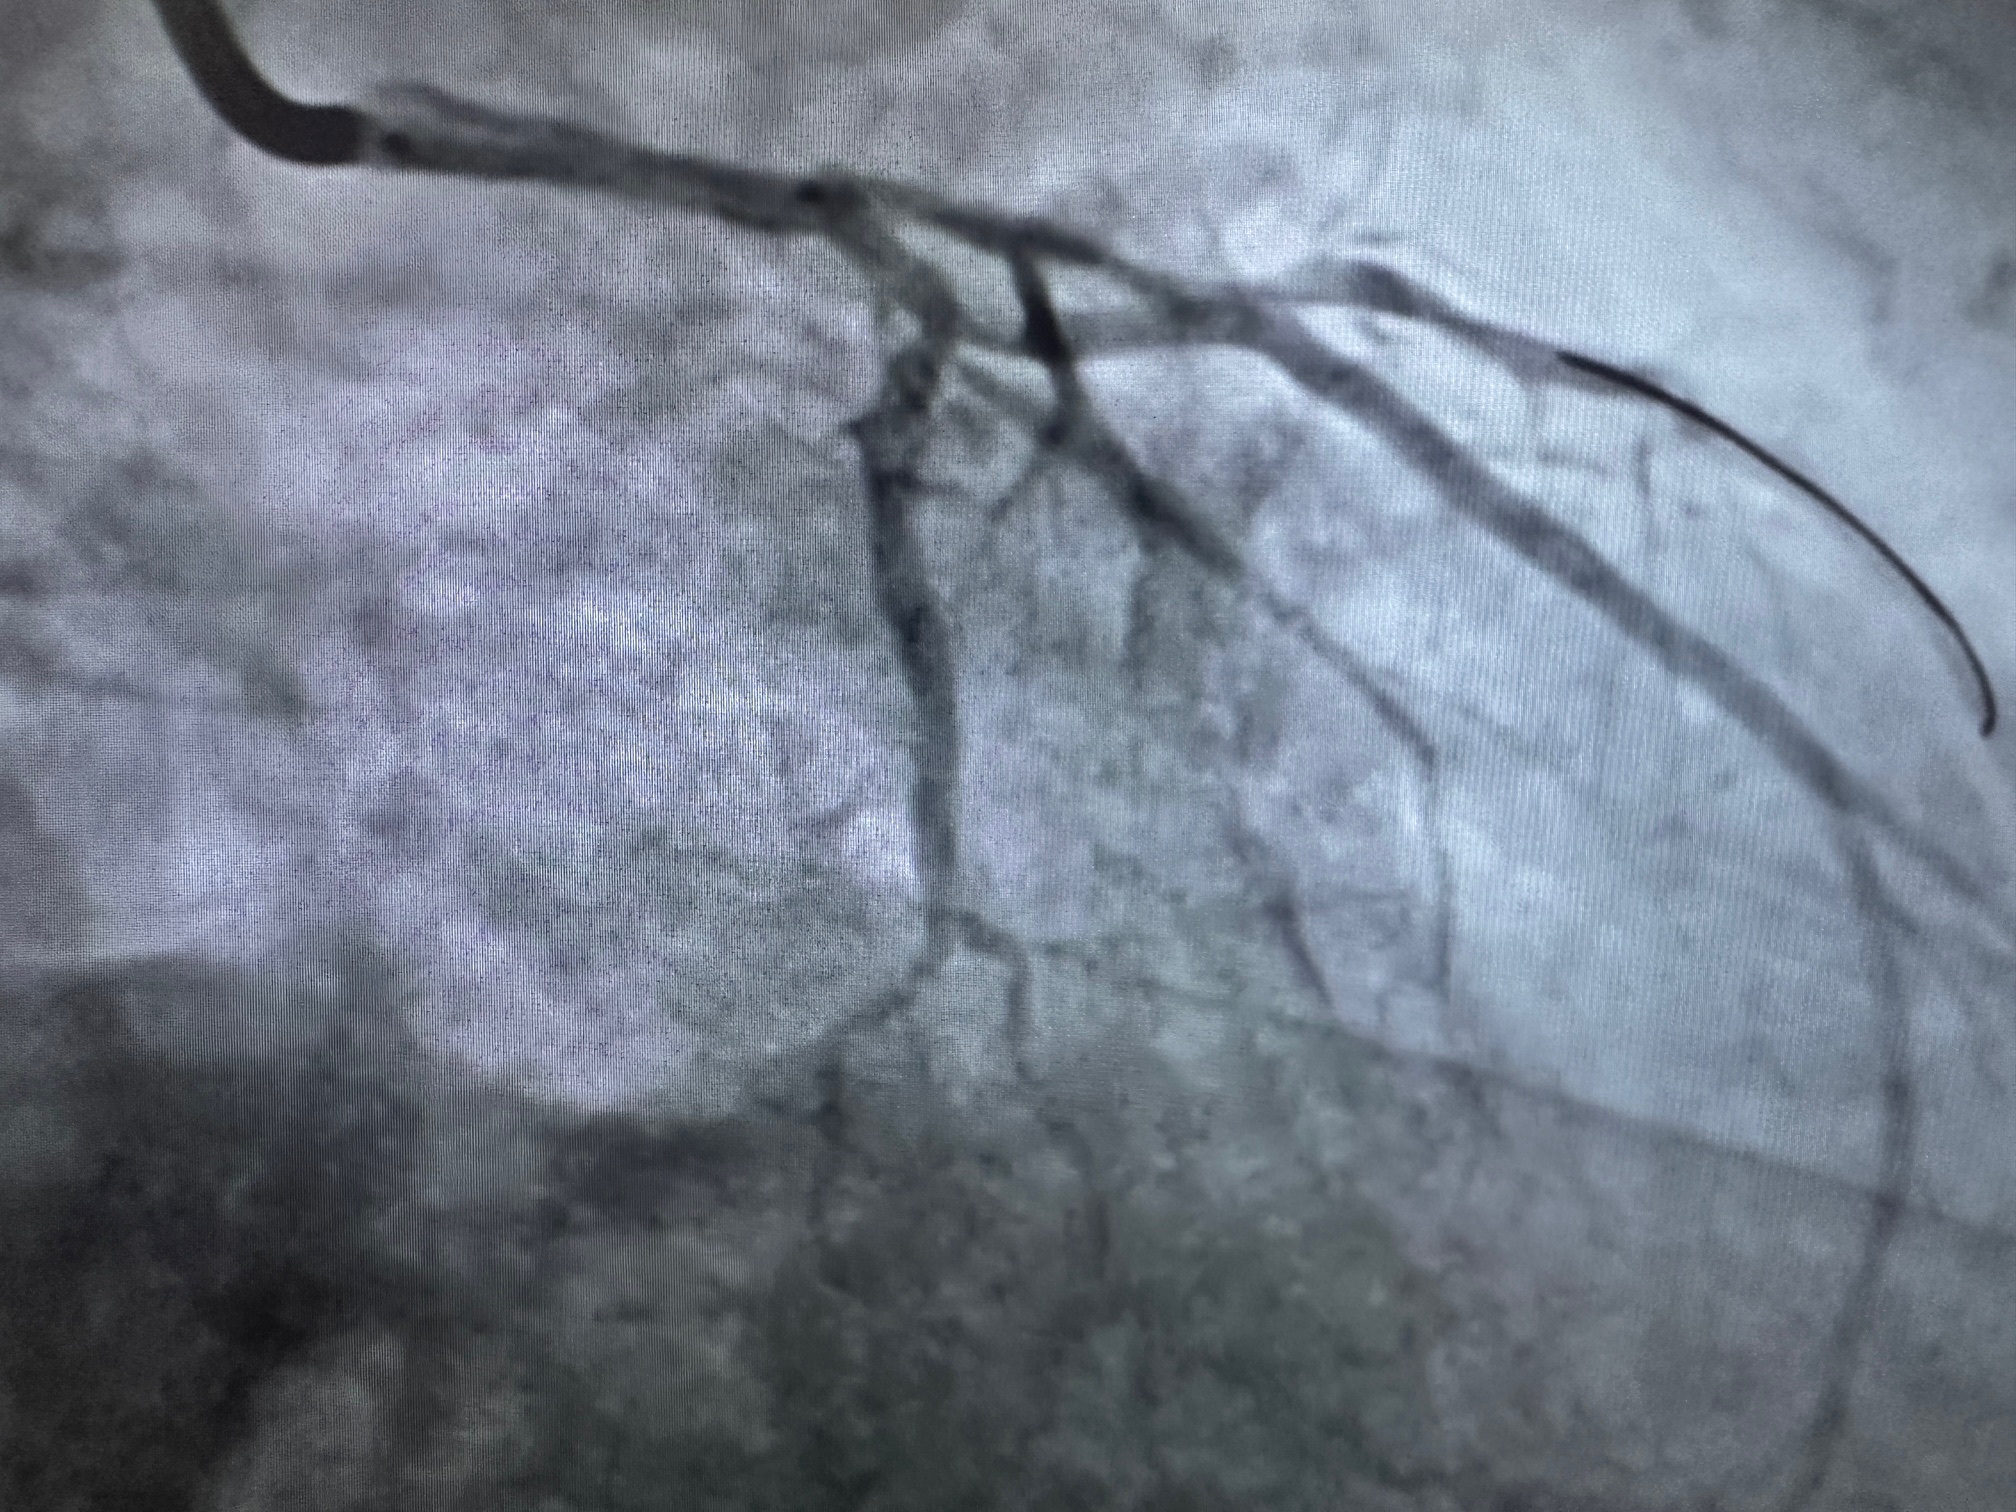

Procedure: Ad hoc PCI to LM-proximal LAD.

- Guiding Catheter: JL Launcher via the right radial artery.

- Complication: Radial artery perforation during catheter insertion.

- Confirmed by contrast extravasation on angiography.

- Small hematoma formation observed at the perforation site.

- Management of Radial Perforation:

- Wire Navigation:

- Advanced a 0.035-inch guidewire into the aorta through the perforated radial artery.

- Introduced a 0.014-inch coronary wire alongside the 0.035-inch wire to maintain distal radial and aortic access for stabilization.

- Balloon-Assisted Technique:

- Positioned a 2.0 mm semi-compliant balloon at the edge of the guiding catheter within the radial artery.

- Inflated the balloon slightly to dilate the perforated segment, facilitating the guiding catheter's smooth passage through the radial artery into the ascending aorta.

- The technique minimized trauma while maintaining radial flow.

- PCI:

- LM-Proximal LAD lesion treated with a drug-eluting stent (DES), achieving TIMI 3 flow post-PCI.

- No further procedural complications.